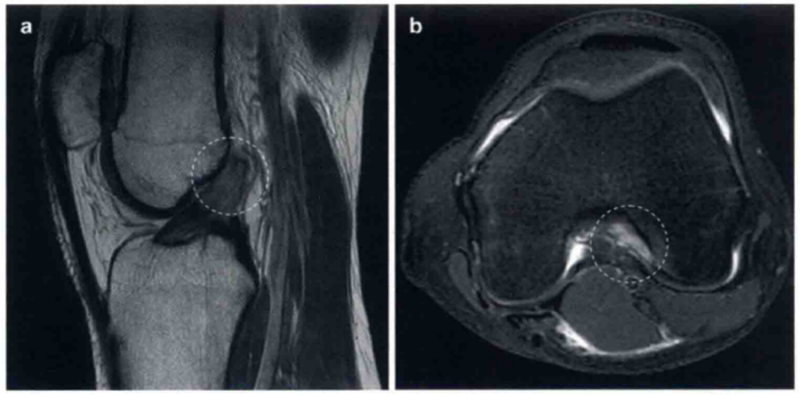

ACL损伤大部分发生于韧带的任何部位,但是最常见的为中间实质部的损伤。韧带信号不显影、不连续或者走行方向异常均提示ACL损伤。图2显示了典型的ACL损伤。与典型的ACL损伤相比,股骨止点处的损伤常常不易察觉(图3),尤其是在矢状位上或者开放低场强的MR1上更易忽略。此时,应该从水平位和冠状位片上去观察分析。尽管ACL结节样和黏液样退变没有明显的膝关节不稳,也无MRI特征性的表现,但是有时仍容易与ACL损伤相混淆(图4)。此外,对于任何类型的韧带慢性损伤,采用MRI诊断时均需慎重,已经瘢痕化但却无功能的ACL也可能在MRI上呈现完整的形态,甚至ACL断裂部位形成的瘢痕搭在PCL上而非股骨止点处(图5)。

图4 a和b显示的为类似ACL损伤的表现。

a显示ACL完整,轻度松散黏液状降解(箭头)。a中ACL为增强的T2高信号,但是走行是正常的,没有不连续的病变,股骨附着点完整。b显示了完整的ACL和ACL腱鞘囊肿(箭头)

图5 显示了之前的ACL陈旧性损伤,随后瘢痕向下搭在PCL上(圆形区),并且在关节镜下证实